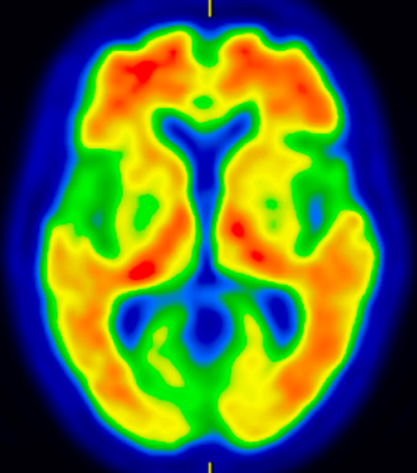

脳血流SPECT(図1):それぞれの認知症に特徴的な血流低下所見を確認して、鑑別診断の精度を高めます。

図1 アルツハイマー型認知症の脳血流SPECT